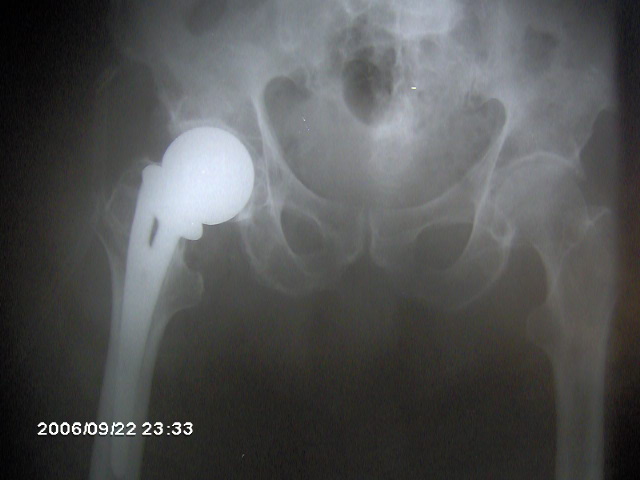

artrosis articular ver más

desgaste de huesos

Cirugía Ortopédica ver más

Para corregir malformaciones o tratar afecciones musculo esqueléticas